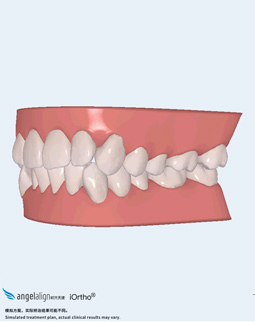

2016-11-22 确定方案

关于牙齿矫正,我只有两个简单的诉求,第一工作的原因限制,我需要更低调的矫正器,只会考虑隐形矫正;第二,由于年龄也在这了,能快一点就最好快点完成吧。但听说成年人用隐形矫正的时间会比较慢,但是麦芽口腔有定制的双膜隐形矫正,据说是奥运冠军同款。由于工作档期比较多,一星期后才又到麦芽口腔,张超主任为我量身定制了矫牙方案,我也更深入的了解了这款麦芽特色牙套,它是利用组合矫治的原理来提速,有薄膜和厚膜两种配合使用,矫牙时间比普通隐形矫正缩短30%,还看到了最终了矫正效果,我很满意。